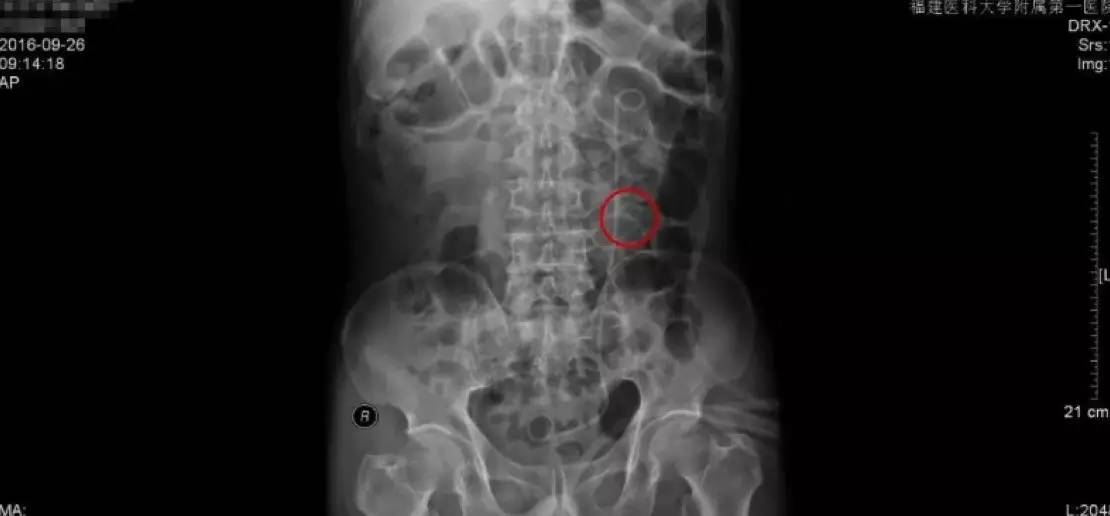

手术前KUB检查报告

手术后KUB检查报告

手术后的复查主要是通过拍KUB,通过与手术前KUB报告的直观对比,从图中可以看到,原来结石的地方,强化的结石已经消失了,左侧可以看到箭头指示的是一根手术后留置的双J管,这根管的目的是为了防止手术后输尿管狭窄黏连。

由于我们的手术是通过输尿管操作的,对输尿管粘膜不同程度有损伤,如果不留置双J管的话,术后容易造成输尿管黏连狭窄,输尿管最细的地方只有0.5cm,所以狭窄是手术后需要注意的并发症。